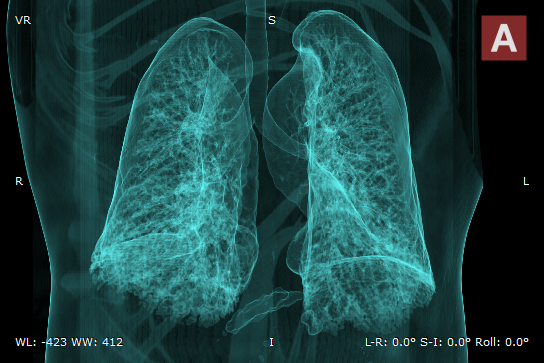

Airways